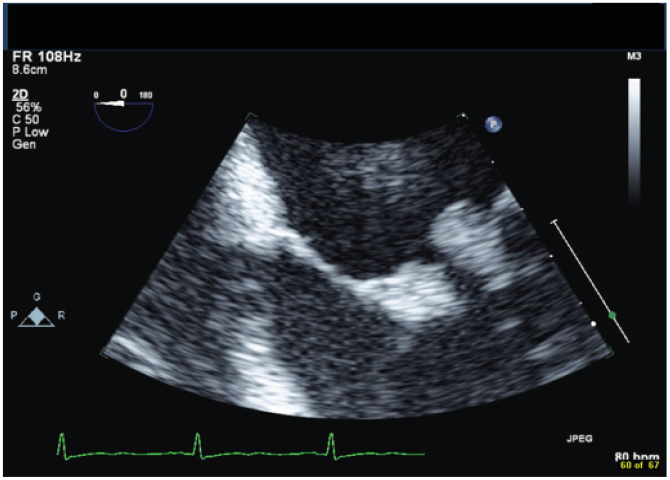

A 42-year-old male with a history of chronic nephrolithiasis presented to the hospital after neighbors found him unconscious at home. On initial evaluation, he was febrile (38.9) with blood pressure of 120/104mmHg. He was severely hypoxic with a sinus rate of 90 beats/minute. His examination revealed multiple abrasions, and he was minimally responsive with a holosystolic murmur at the apex. His electrocardiogram showed normal sinus rhythm with no acute ST-T wave changes. Laboratory data revealed a white cell count of 17.4/nl, platelet count of 109/nl, lactate level of 4.8 mmol/l and creatinine of 1.57mg/dl. Computed tomography of the head revealed multiple regions of acute infarction involving the right inferior cerebellum, left occipital lobe with mass effect on the left occipital horn. He underwent a transthoracic echocardiogram that showed vegetations on both the mitral and aortic valve. He underwent a trans-esophageal echocardiogram, which demonstrated multiple vegetations on the mitral (Figure 1), aortic (Figure 2) and pulmonic valves (Figure 3) with severe pulmonic, mitral and aortic insufficiency (Figure 4 & 5). Despite negative urine cultures, serial blood cultures grew Aerococcus urinae and he was given appropriate IV antibiotics. He was evaluated for possible valvular surgery and was deemed to be a poor surgical candidate. He later developed splenic and renal infarcts followed by significant hemodynamic instability requiring vasopressors and ultimately succumbed to his illness after he developed multi organ failure and disseminated intravascular coagulation.